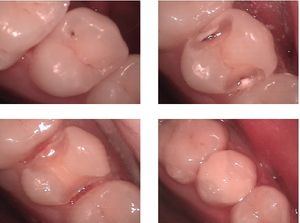

어금니용 올 세라믹 치과 온레이

도재(Dental porcelain, Dental ceramic)는 인레이, 온레이, 라미네이트, 크라운 등 다양한 형태로 제작 가능하다.[26] 전체 도재 수복물은 색상과 반투명도가 자연 치아 법랑질을 모방하기 때문에 특히 선호된다.

금속-도재는 크라운 또는 브릿지의 강도를 제공하는 데 사용되며, 도재와 금속의 조합으로 인해 매우 강하고 내구성이 뛰어나며 마모에 강하다.[18]

전산화 치과(CAD/CAM 기술)에서는 부분적으로 소결된 상태로 판매되는 가공 가능한 세라믹을 사용하며, 가공 후 다시 소성하여 단단한 세라믹을 형성한다.[18] 사용되는 재료로는 유리 결합 도재, 디실리케이트 리튬 유리-세라믹, 상 안정화 지르코니아 등이 있다. 소결 지르코늄 산화물은 높은 강도와 파괴 인성으로 인해 구치부 크라운 및 브릿지, 임플란트 어버트먼트 및 근관 핀에 사용 가능하다. 디실리케이트 리튬은 구치에 사용하기 위해 필요한 파절 저항성을 가지고 있다.[19]